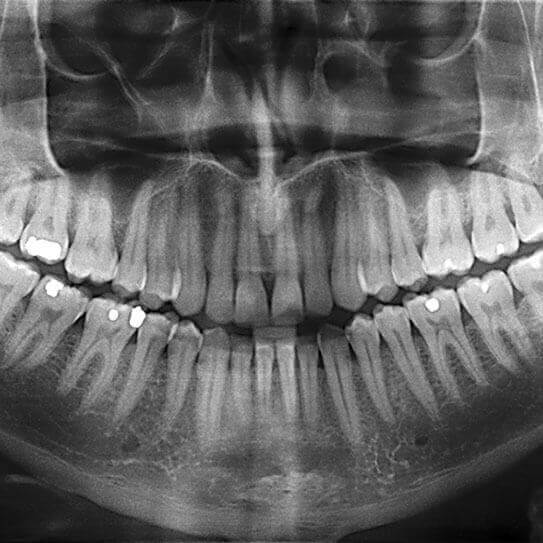

Dental X-Rays: It’s Time For Your Close-Up

IF WE ASKED you to list three things that happen in a typical dental exam, dental X-rays would probably be one of…